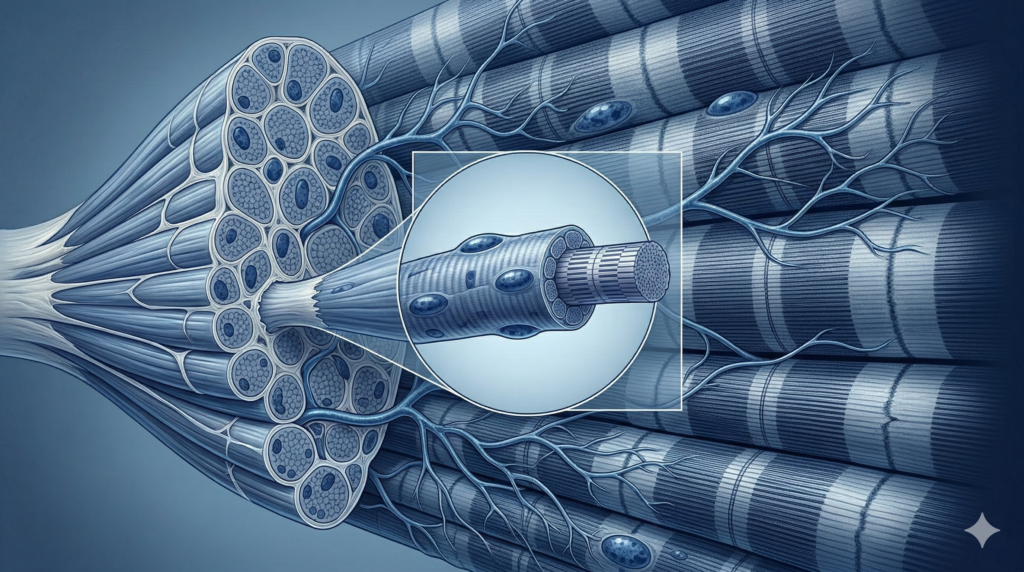

Miopatías inflamatorias

Diagnóstico diferencial de polimiositis, dermatomiositis y miopatías asociadas a anticuerpos específicos. Seguimiento clínico y de imagen para valoración de respuesta al tratamiento.